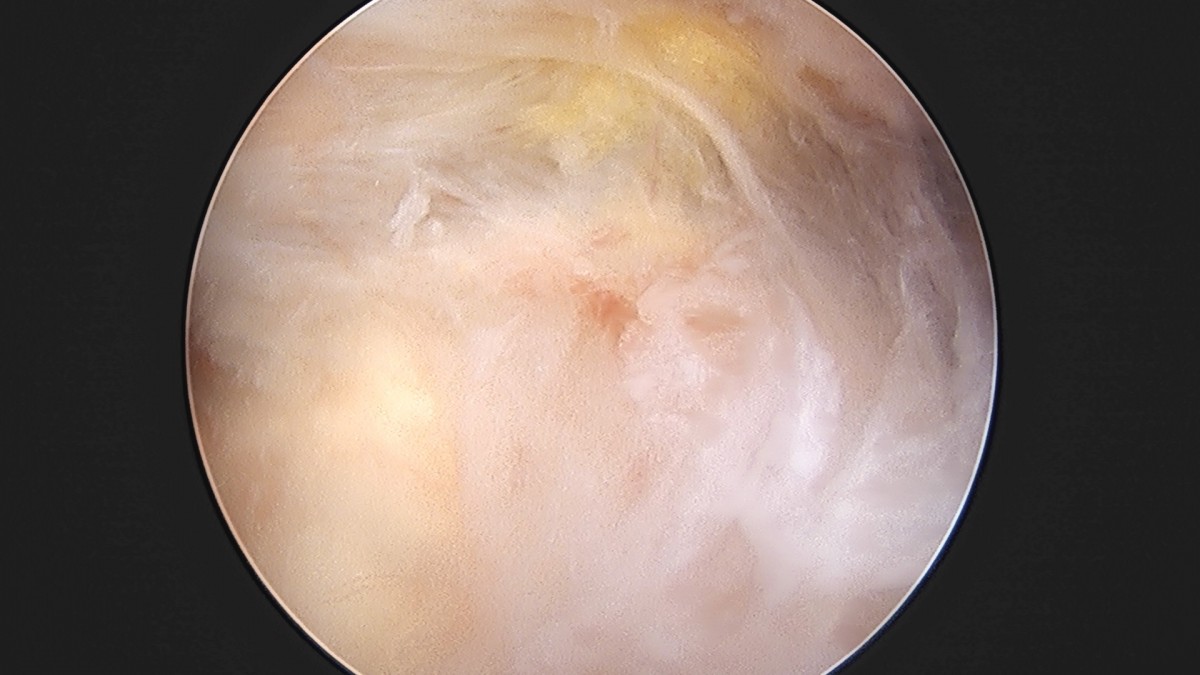

이재상원장님 어깨 견봉하 감압술 및 관절낭 이완술 양명O 환자

dae765e4d9ac96aee867c9d6292d8784_1758004382_1147.jpg